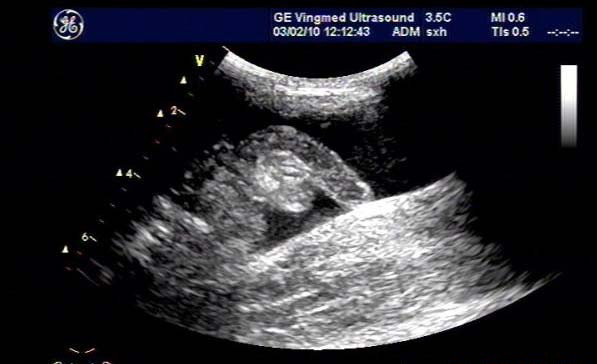

闌尾炎是美國兒童常見的疾病,發(fā)生率持續(xù)增加;雖然CT是最常用來評估疑似闌尾炎患者之癥狀的影像技術(shù),但它與顯著增加放射線暴露有關(guān),而超聲檢查不會有放射線暴露。

研究目標(biāo)是,兒童急性闌尾炎時,使用超聲檢查作為第一種影像檢查方式時,確認(rèn)是否會增加復(fù)雜性闌尾炎比率與住院天數(shù)(LOS)。